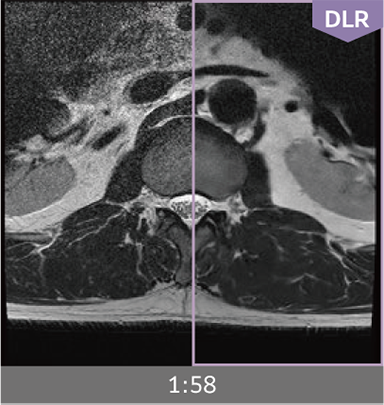

Combining high-speed imaging technology with Deep Learning reconstruction technology*3, Advanced Reconstruction with Deep Learning Synergy DLR, enables shorter exams and reduces image noise.

Images can be obtained at high speed by combining two proprietary technologies: IP-RAPID, which reduces imaging time while maintaining image quality, and Synergy DLR, which uses deep learning technology*6 to improve image quality

Under-sampling reduces imaging time, and iterative reconstruction with IP-RAPID reduces noise and artifacts.

In addition, Synergy DLR, an image reconstruction technology utilizing deep learning technology, further eliminates noise and produces images that are easier to use in making a diagnosis.